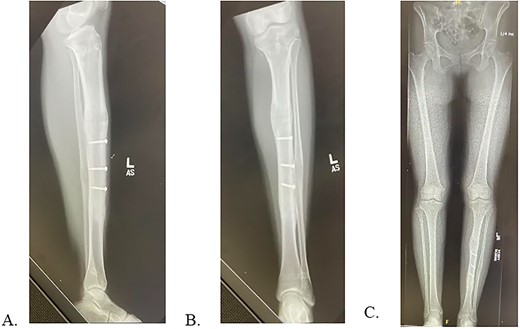

Final radiographs showed adequate alignment, internal fixation of the tibial osteotomy, and complete hardware removal aside from the three new fixation screws (Fig. 4A). The incisions were closed, dressed and the leg was immobilized in a Controlled Ankle Motion (CAM) boot. The patient spent six weeks non-weight bearing but was able to return to work without any pain or limping at three months post implant removal (Fig. 4B). Final 12-months follow-up demonstrated radiographically healed osteotomy site and maintained equal limb lengths and alignment (Fig. 5A-C).

A: 12 months postoperative PRECICE explantation with osseous union at osteotomy site of lateral left tibia. B: 12 months postoperative PRECICE explantation with osseous union at osteotomy site of AP left tibia. C: 12 months postoperative PRECICE explantation with equal limb lengths and alignment.